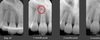

Trauma: root fracture (cervical or mid 1/3)